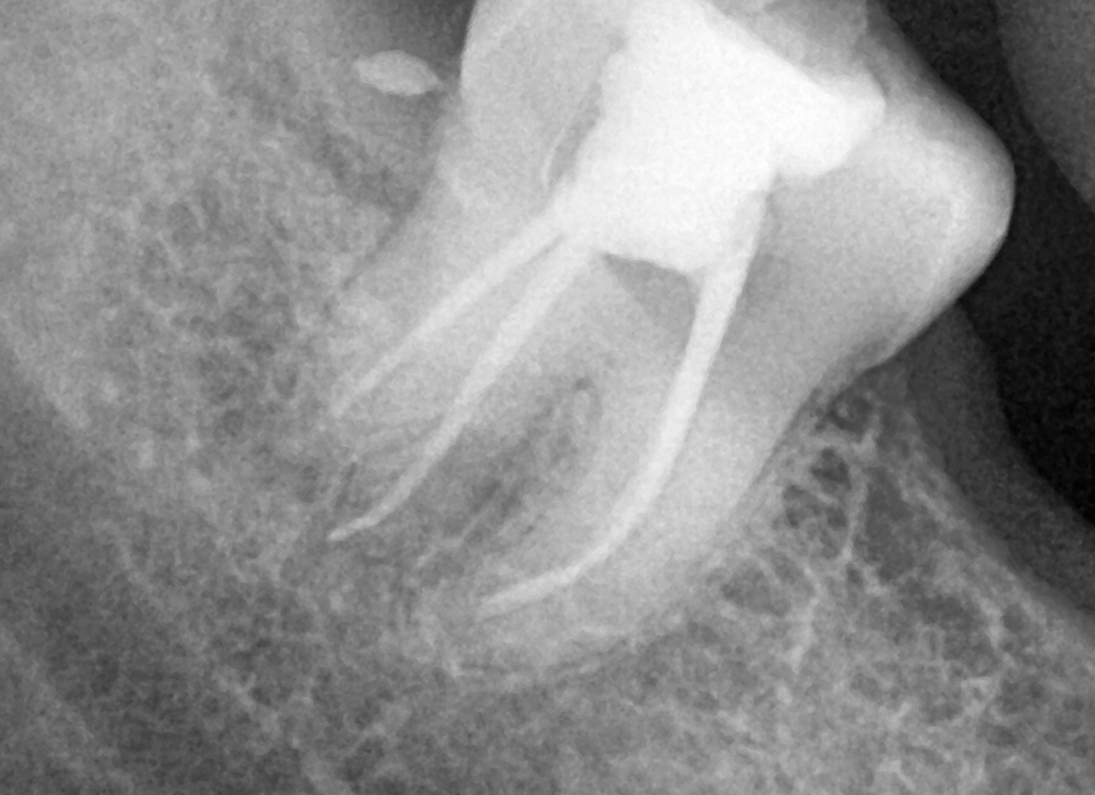

• A diagnosis is made for the tooth with percussion, palpation and cold tests and an x-ray.

• Measurements of the length of the root canal is noted and take x-rays to confirm the length. Ensuring that the entire length of the root canal is cleaned.

• Irrigate the tooth with antibacterial solutions, dry the tooth, Gutta Percha (rubber points) should be placed into the root canals.

• Once the Gutta Percha is placed, a temporary filling on the tooth or a permanent filling on the tooth can be placed.